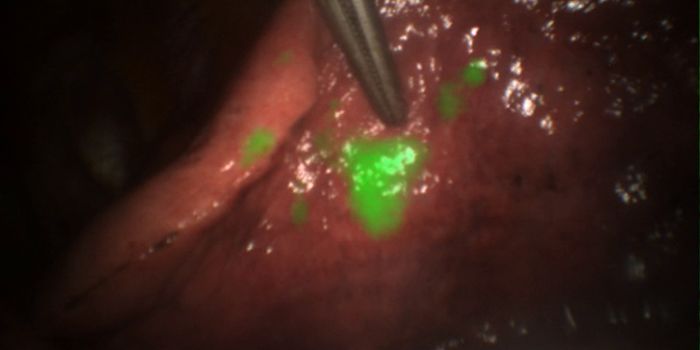

Surgery Shouldn't be a Guessing Game

Surgically removing tumors is an effective way to treat cancer. However, in cases where the cancer periphery is unclear, ...

Brain Tumors All Aglow

In as much as 50 percent of operations to remove brain tumors, some cancerous bits are left behind and the cancer makes ...